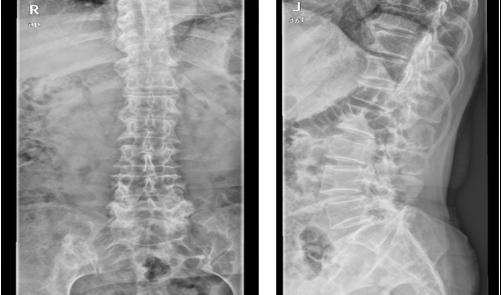

术前